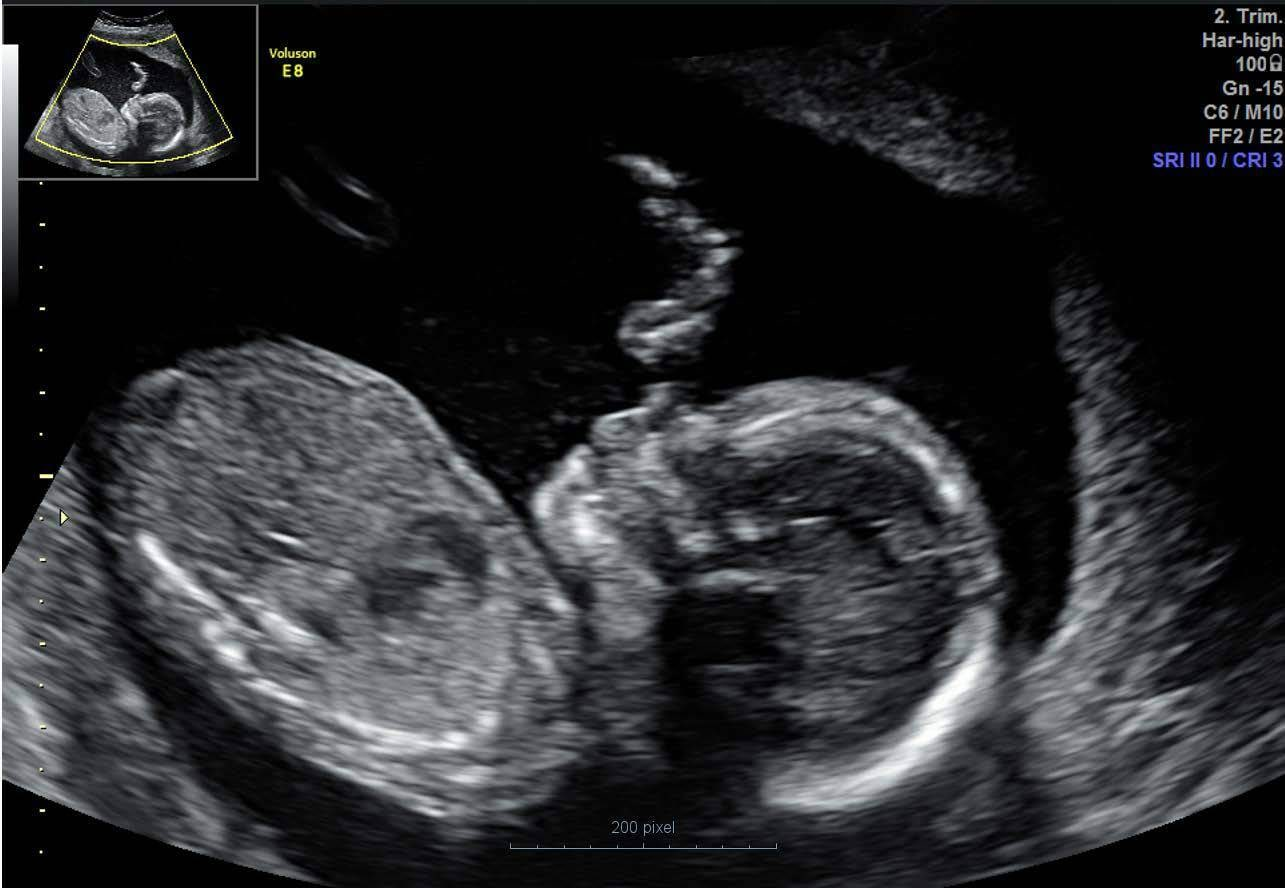

Ultrahelipilt lootest

Pildil olev isik on õpiku autorile teada.